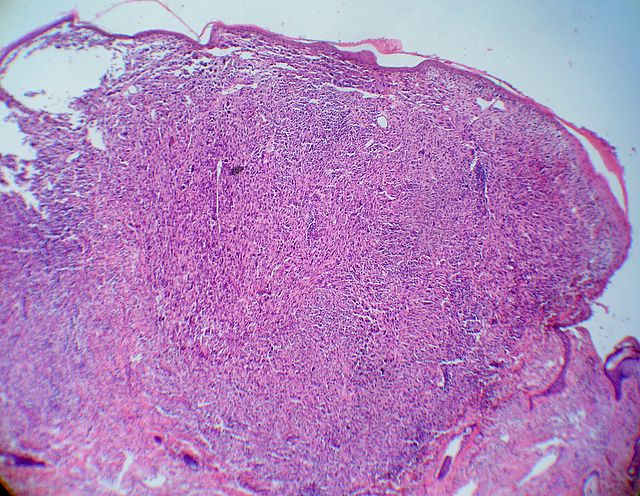

Descripcion histologica

Diagnostico